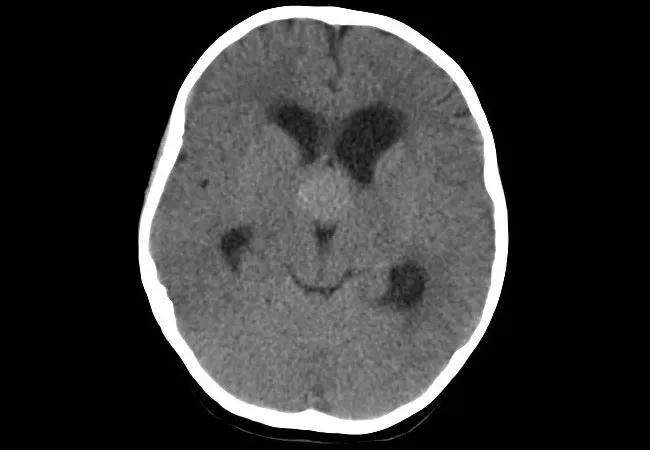

Imaging Children With Papilledema: CT Alone May Suffice If Neurologic Evaluation Is Normal

For children who present with papilledema and no red flags for underlying tumor or thrombosis, imaging by CT alone — without MRI follow-up — may be adequate. That’s the conclusion of a review of CT and MRI findings among a series of Cleveland Clinic pediatric patients who were diagnosed with papilledema, idiopathic intracranial hypertension, brain tumor or cerebral venous thrombosis. The research was presented at the 2020 virtual meeting of the American Academy of Neurology this spring.

“MRIs are costly and often require general anesthesia in children, so avoiding them when they are not essential reduces needless expense and risk,” says senior author Gary Hsich, MD, a pediatric neurologist in Cleveland Clinic’s Center for Pediatric Neurosciences. “Our data support the notion that, in select children with papilledema — i.e., those with a normal neurologic examination — CT provides adequate imaging evaluation.”

Papilledema, a sign of increased intracranial pressure, can be found serendipitously in children during a routine eye check or during evaluation for vision changes, headaches or nausea. Although brain MRI is often performed to rule out underlying brain tumor or cerebral venous thrombosis, few data exist, especially in the pediatric population, to support the necessity of MRI over CT to diagnose these rare entities.